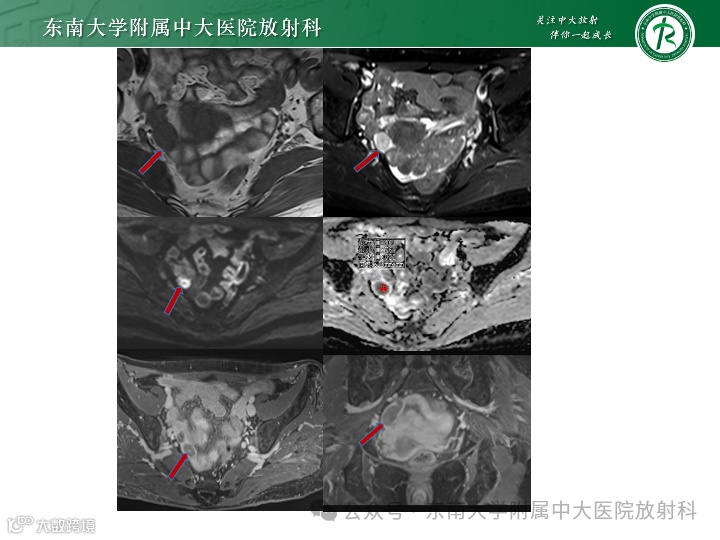

病例2

女,27岁 -

主诉:腹胀1周 -

现病史:1周前自觉腹胀,有恶心,无明显腹痛呕吐,无异常阴道出血,无腹泻便秘等,于外院就诊查CA125:791.8U/ml,左侧卵巢内见一19*18mm液性暗区,腹盆腔见深约65mm液性暗区。遂住院于腹腔穿刺,每日约1000ml左右,淡黄色,腹水脱落细胞可见淋巴细胞。今为求进一步诊治来我院就诊

影像学表现